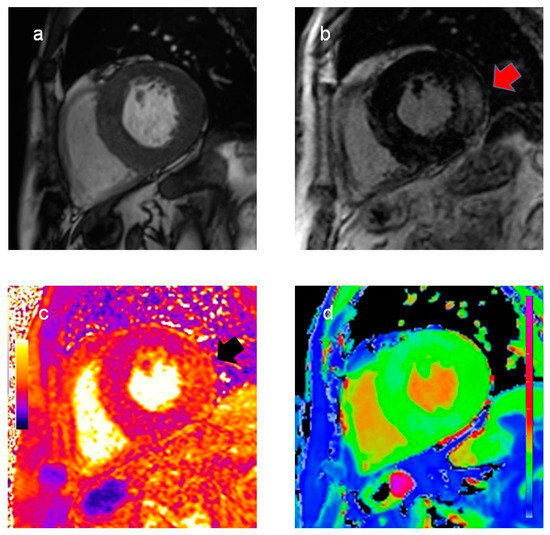

Cardiac magnetic resonance (CMR) showed severe biventricular hypertrophy with reduced native T1 values, suggesting myocardial glycosphingolipid storage. The left ventricular mass index was 198.4 g/m2. Extensive late gadolinium enhancement was also detected in the infero-lateral wall, with an increased T2 value indicating myocardial edema (Figure 1).

Figure 1. Cardiac magnetic resonance findings. Cine (a) and late gadolinium enhancement images (b), T2 (c), and T1 map (d) in basal short-axis view. Significant biventricular hypertrophy with extensive late gadolinium enhancement in the infero-lateral wall ((b), red arrow). Increased T2 values in the infero-lateral wall ((c), black arrow) indicate myocardial inflammation. Reduced native T1 values (d), suggesting myocardial glycosphingolipid storage, are a typical finding in Fabry disease.